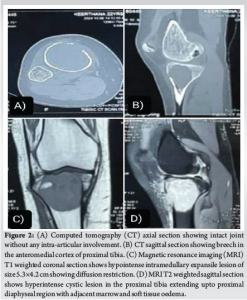

Computed tomography screening (Fig. 2 a and b) was done to rule out the involvement of cortical breech, which confirmed the anterior cortical breech over the proximal tibia.

Magnetic resonance imaging of the right knee-T1 weighted (Fig. 2c) shows a hypointense intramedullary expansile lesion of size 5.3 × 4.2 cm showing diffusion restriction. T2-weighted (Fig. 2d) shows a hyperintense cystic lesion extending up to the proximal diaphyseal region with adjacent marrow and soft tissue oedema. After thorough pre-operative planning, the patient was taken up for surgery. Proximal tibia anteromedial approach was used for the patient, keeping the possibility of anteromedial cortical breech, and soft tissues were dissected. The proximal tibia was exposed to trace the boundaries of the lesion. The anteromedial cortex was found to be breached and found to be a multiloculated cystic mass with haemorrhage and blood-filled cavities (Fig. 3a). The involved cortex was nibbled out to enter the cavity of the lesion. Complete, thorough curettage was done with the bone gouge. The inner and outer margins are curetted with the highspeed burr. The cavity was thoroughly washed with hydrogen peroxide repeatedly for thermal necrosis of the remnant tumor cells (Fig. 3b). Subchondral bone was found to be intact which confirmed that the joint was preserved. Using sandwich technique, cavity was first filled with gel foam, polymethylmethacrylate (PMMA) bone cement and gel foam optimally to fill up the dead space in the cavity (Fig. 3c and d). Once the cement was set, wound wash was given to the surrounding soft tissues. The curetted tissue sample was sent for culture and histopathological studies. Intraoperative and post-operative periods were uneventful.